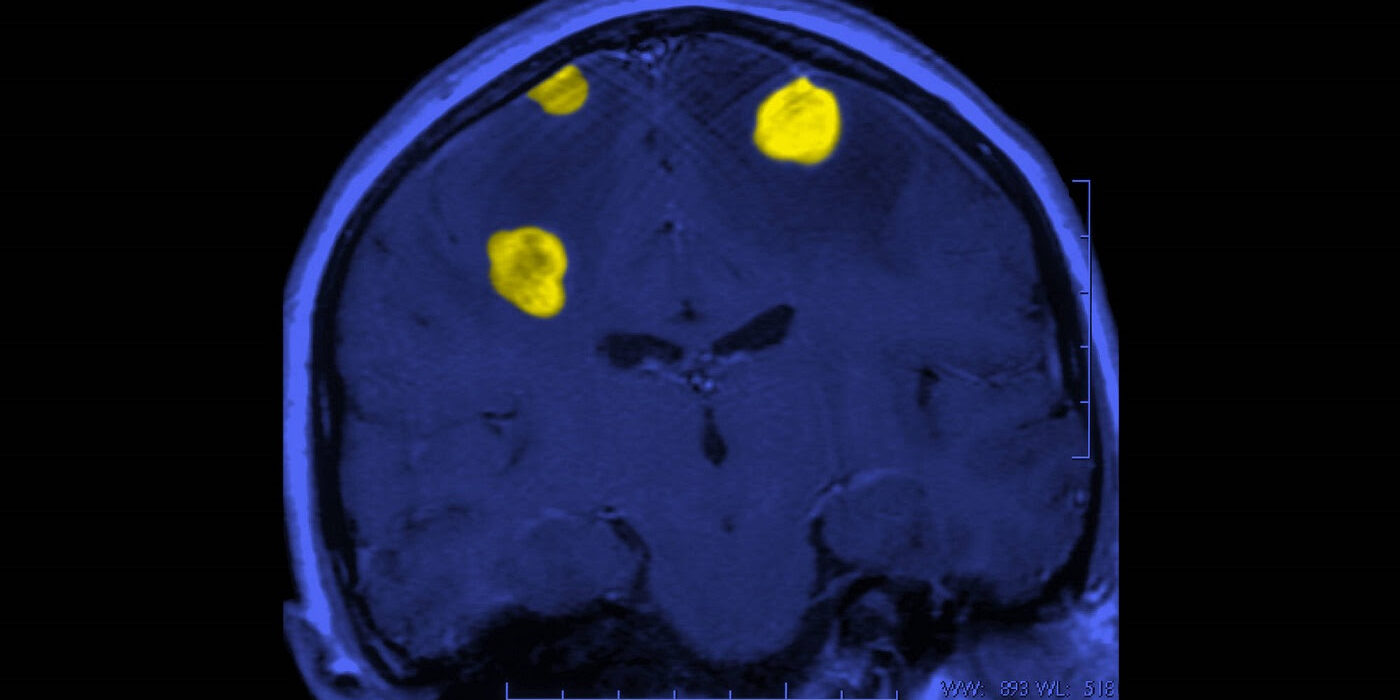

Los expertos nos explican siete de los tratamientos más avanzados, que han brindado esperanza a pacientes con tumores cerebrales

Dependiendo de los resultados, el paciente puede someterse a una o más pruebas mediante tomografía computarizada (TC), resonancia magnética, tomografía por emisión de positrones (PET) u otros tipos de escáneres cerebrales.

El tratamiento para los tumores cerebrales se basa en factores individuales, como la edad, la salud general y el historial médico, así como las características del tumor (tipo, ubicación y tamaño) y la probabilidad de que el tumor se propague o recurra.